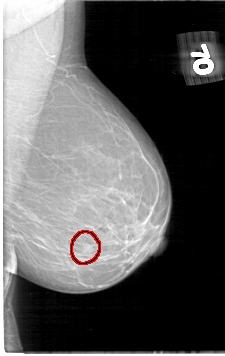

D_4060_1.RIGHT_MLO

LEFT_CC LINES 5386 PIXELS_PER_LINE 3301 BITS_PER_PIXEL 12 RESOLUTION 43.5 OVERLAY

FILE: D_4060_1.LEFT_CC.OVERLAY

TOTAL_ABNORMALITIES 1

ABNORMALITY 1

LESION_TYPE MASS SHAPE ROUND MARGINS OBSCURED

ASSESSMENT 0

SUBTLETY 4

PATHOLOGY BENIGN

TOTAL_OUTLINES 1

BOUNDARY